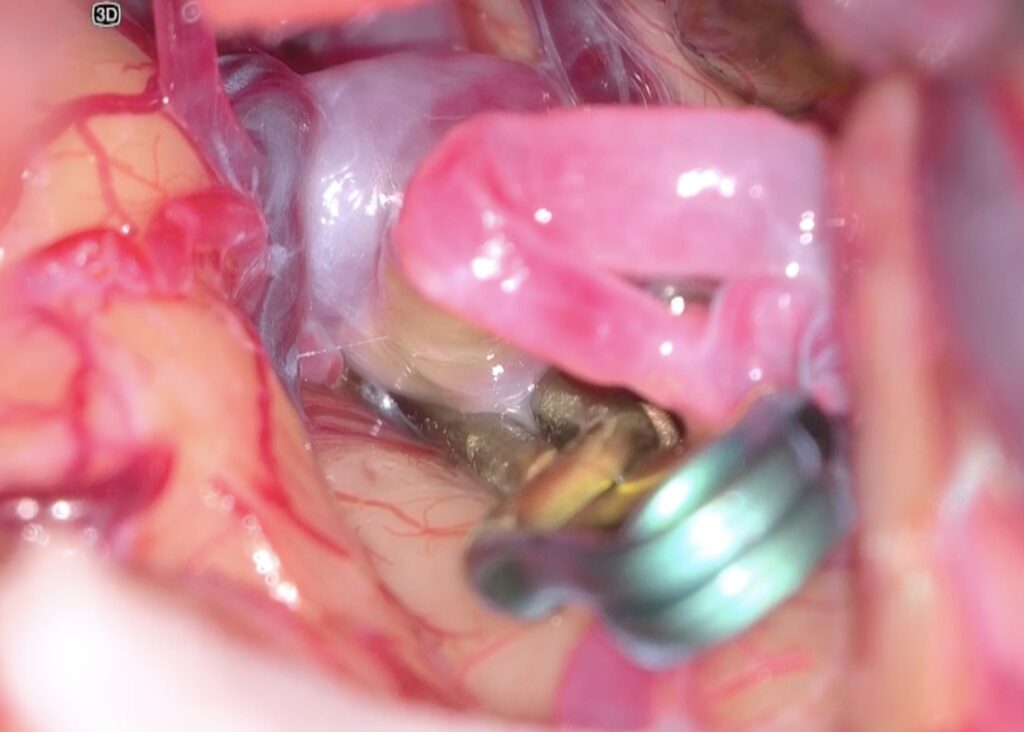

コンビネーションクリップでクリップしました。最終クリップに至るまでに、両側M2が十分流れるように書け直しを2回ほど行いました。ドームをしっかり剥離してぶらぶらにすること、クリップを一回でなくベストクリップになるまで何度もやり直すのが京大伝統の教えです。

ICGやドップラーで確認し、閉創です。オーブアイは色調や焦点深度がフットスイッチで自在に変えられるのが利点です。覚醒良好で、後遺症なく治療できました。